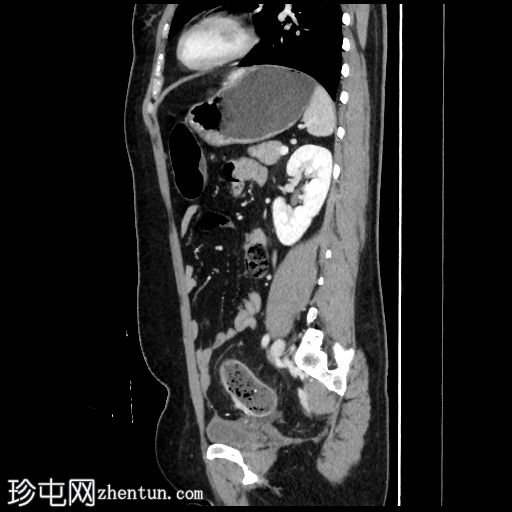

矢状位增强扫描(门静脉期)